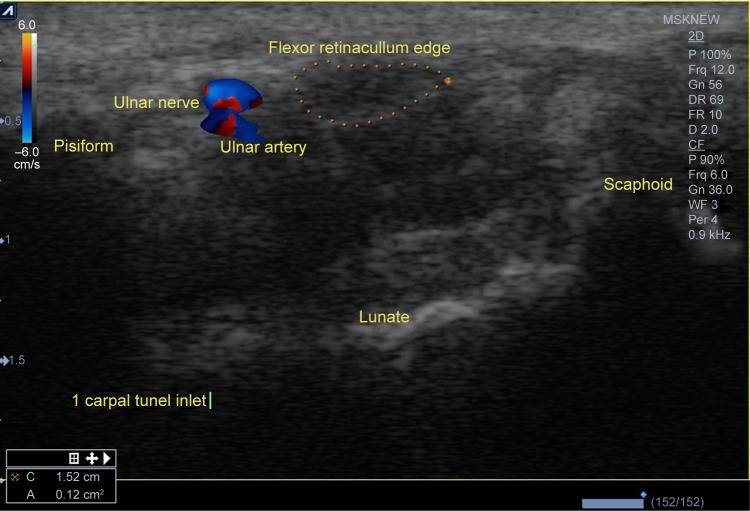

Inlet area (eg, the level of pisiform and scaphoid) (Figure 1).

Figure 1.

Inlet area (eg, the level of pisiform and scaphoid).